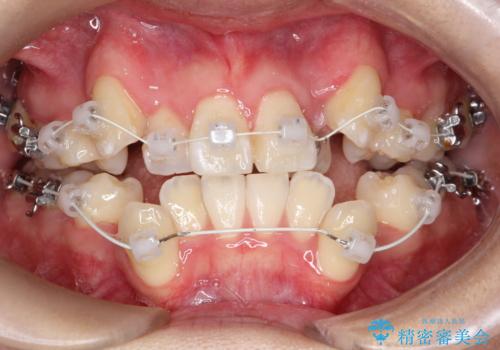

【ワイヤー矯正】八重歯 歯のでこぼこを治したい!

- 治療計画

- 「歯のでこぼこを治したい」を主訴に来院された患者様です。 上下ともに、歯のでこぼこが強く、上下左右4の抜歯をし、ワイヤー矯正で治療を行いました。

かなり綺麗に並ぶ事ができ大変満足していただけました。

叢生量がかなり多かったのですが、歯肉退縮も失活歯も無くとても綺麗な歯並びになりました。